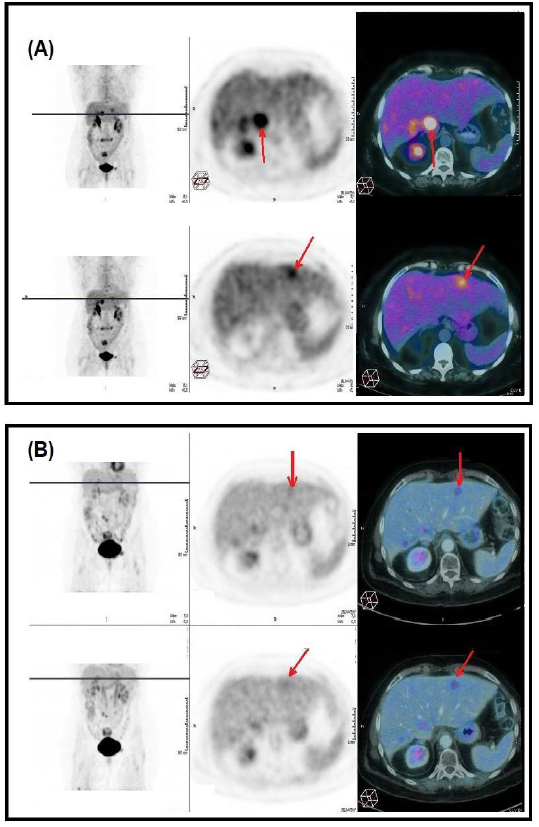

Results reported IDH1, FOXP1 and TP53 mutations, but no therapy with potential clinical benefit was identified. This test also showed stable microsatellite status and low tumor mutation burden. Immunohistochemistry analysis for programmed cell death 1 ligand (PD-L1) expression (SP263 assay) was also negative. Hence, a combination of leucovorin, 5-fluorouracil and irinotecan (FOLFIRI) was started, but the disease progressed after 7 cycles. Considering a satisfactory performance status (ECOG 1) maintained during this period, the patient started regorafenib 120 mg orally per day. After 3 months of treatment, PET scan showed objective metabolic response in all secondary lesions. The patient has been receiving regorafenib for 16 months and remains with stable disease and excellent tolerance to treatment.

Figure 1: (A) PET scan after 7 cycles of FOLFIRI showing higher FDG uptake in 2 hepatic nodules. (B) Image control after 16 months of regorafenib treatment indicating metabolic response and stable morphological lesions.